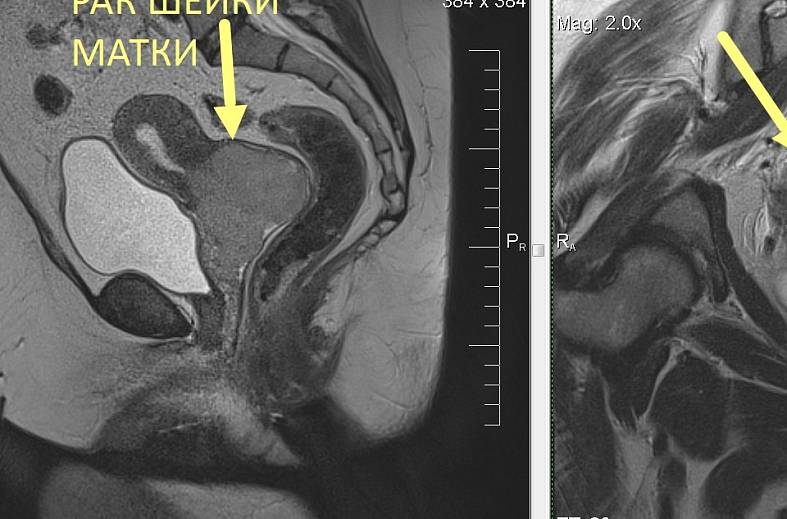

КТ-исследование абсцесса малого таза: Визуализация и диагностика

Раздел: Фотоальбом решений